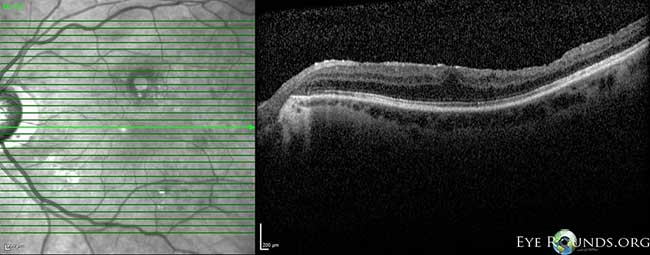

Fig 3-8: OCT OS: scant ERM remnants nasal to the fovea; thinning temporal in areas of prior membrane peeling.